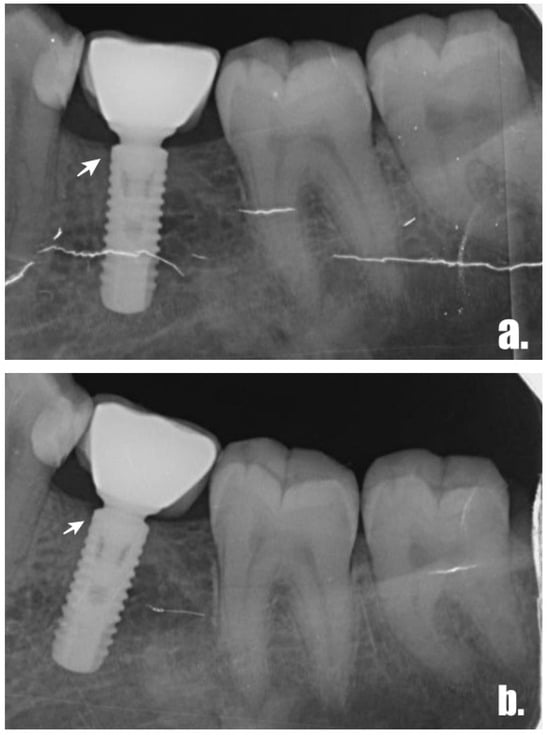

2.3. Radiographic Examination and Measurements